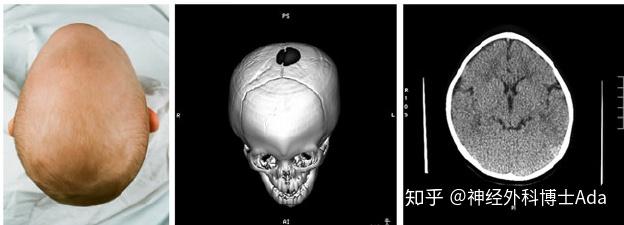

头型异常之二——三角头畸形(额缝早闭)

1, 额缝早闭典型的表现为三角头畸形,前额正中锋利的龙骨样突起,并有

颅缝早闭-三角头畸形的手术前后_对比